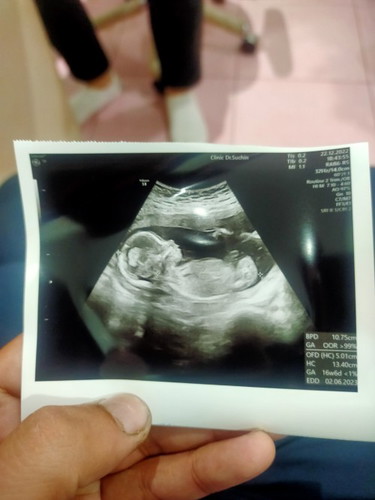

ขอสอบถามแม่ๆหน่อยค้า ใครพอจะมองออกบ้าง👶

อยากทราบว่าน้องเพศอะไรค่ะ แม่ลุ้นมากค้า ตื่นเต้น ป่ะป๊าน้องรู้แล้วเพราะแอบยิบตากับลุงหมอ🤣🤣 ปล.#หมอกับป่ะป๊าไม่บอกแม่ แม่ภาวนาให้เป็นเพศชายค้า เพราะที่บ้านมี2สาว ตุ๊กตาหน้ารถแล้วค่า 2สาวที่บ้านก้อยากได้น้องชายบ้าง🥰 #ใครพอมองรูปแล้วทราบบ้างค้า🤣 #ทีมมิถุนา65 #คุณแม่ลูก3